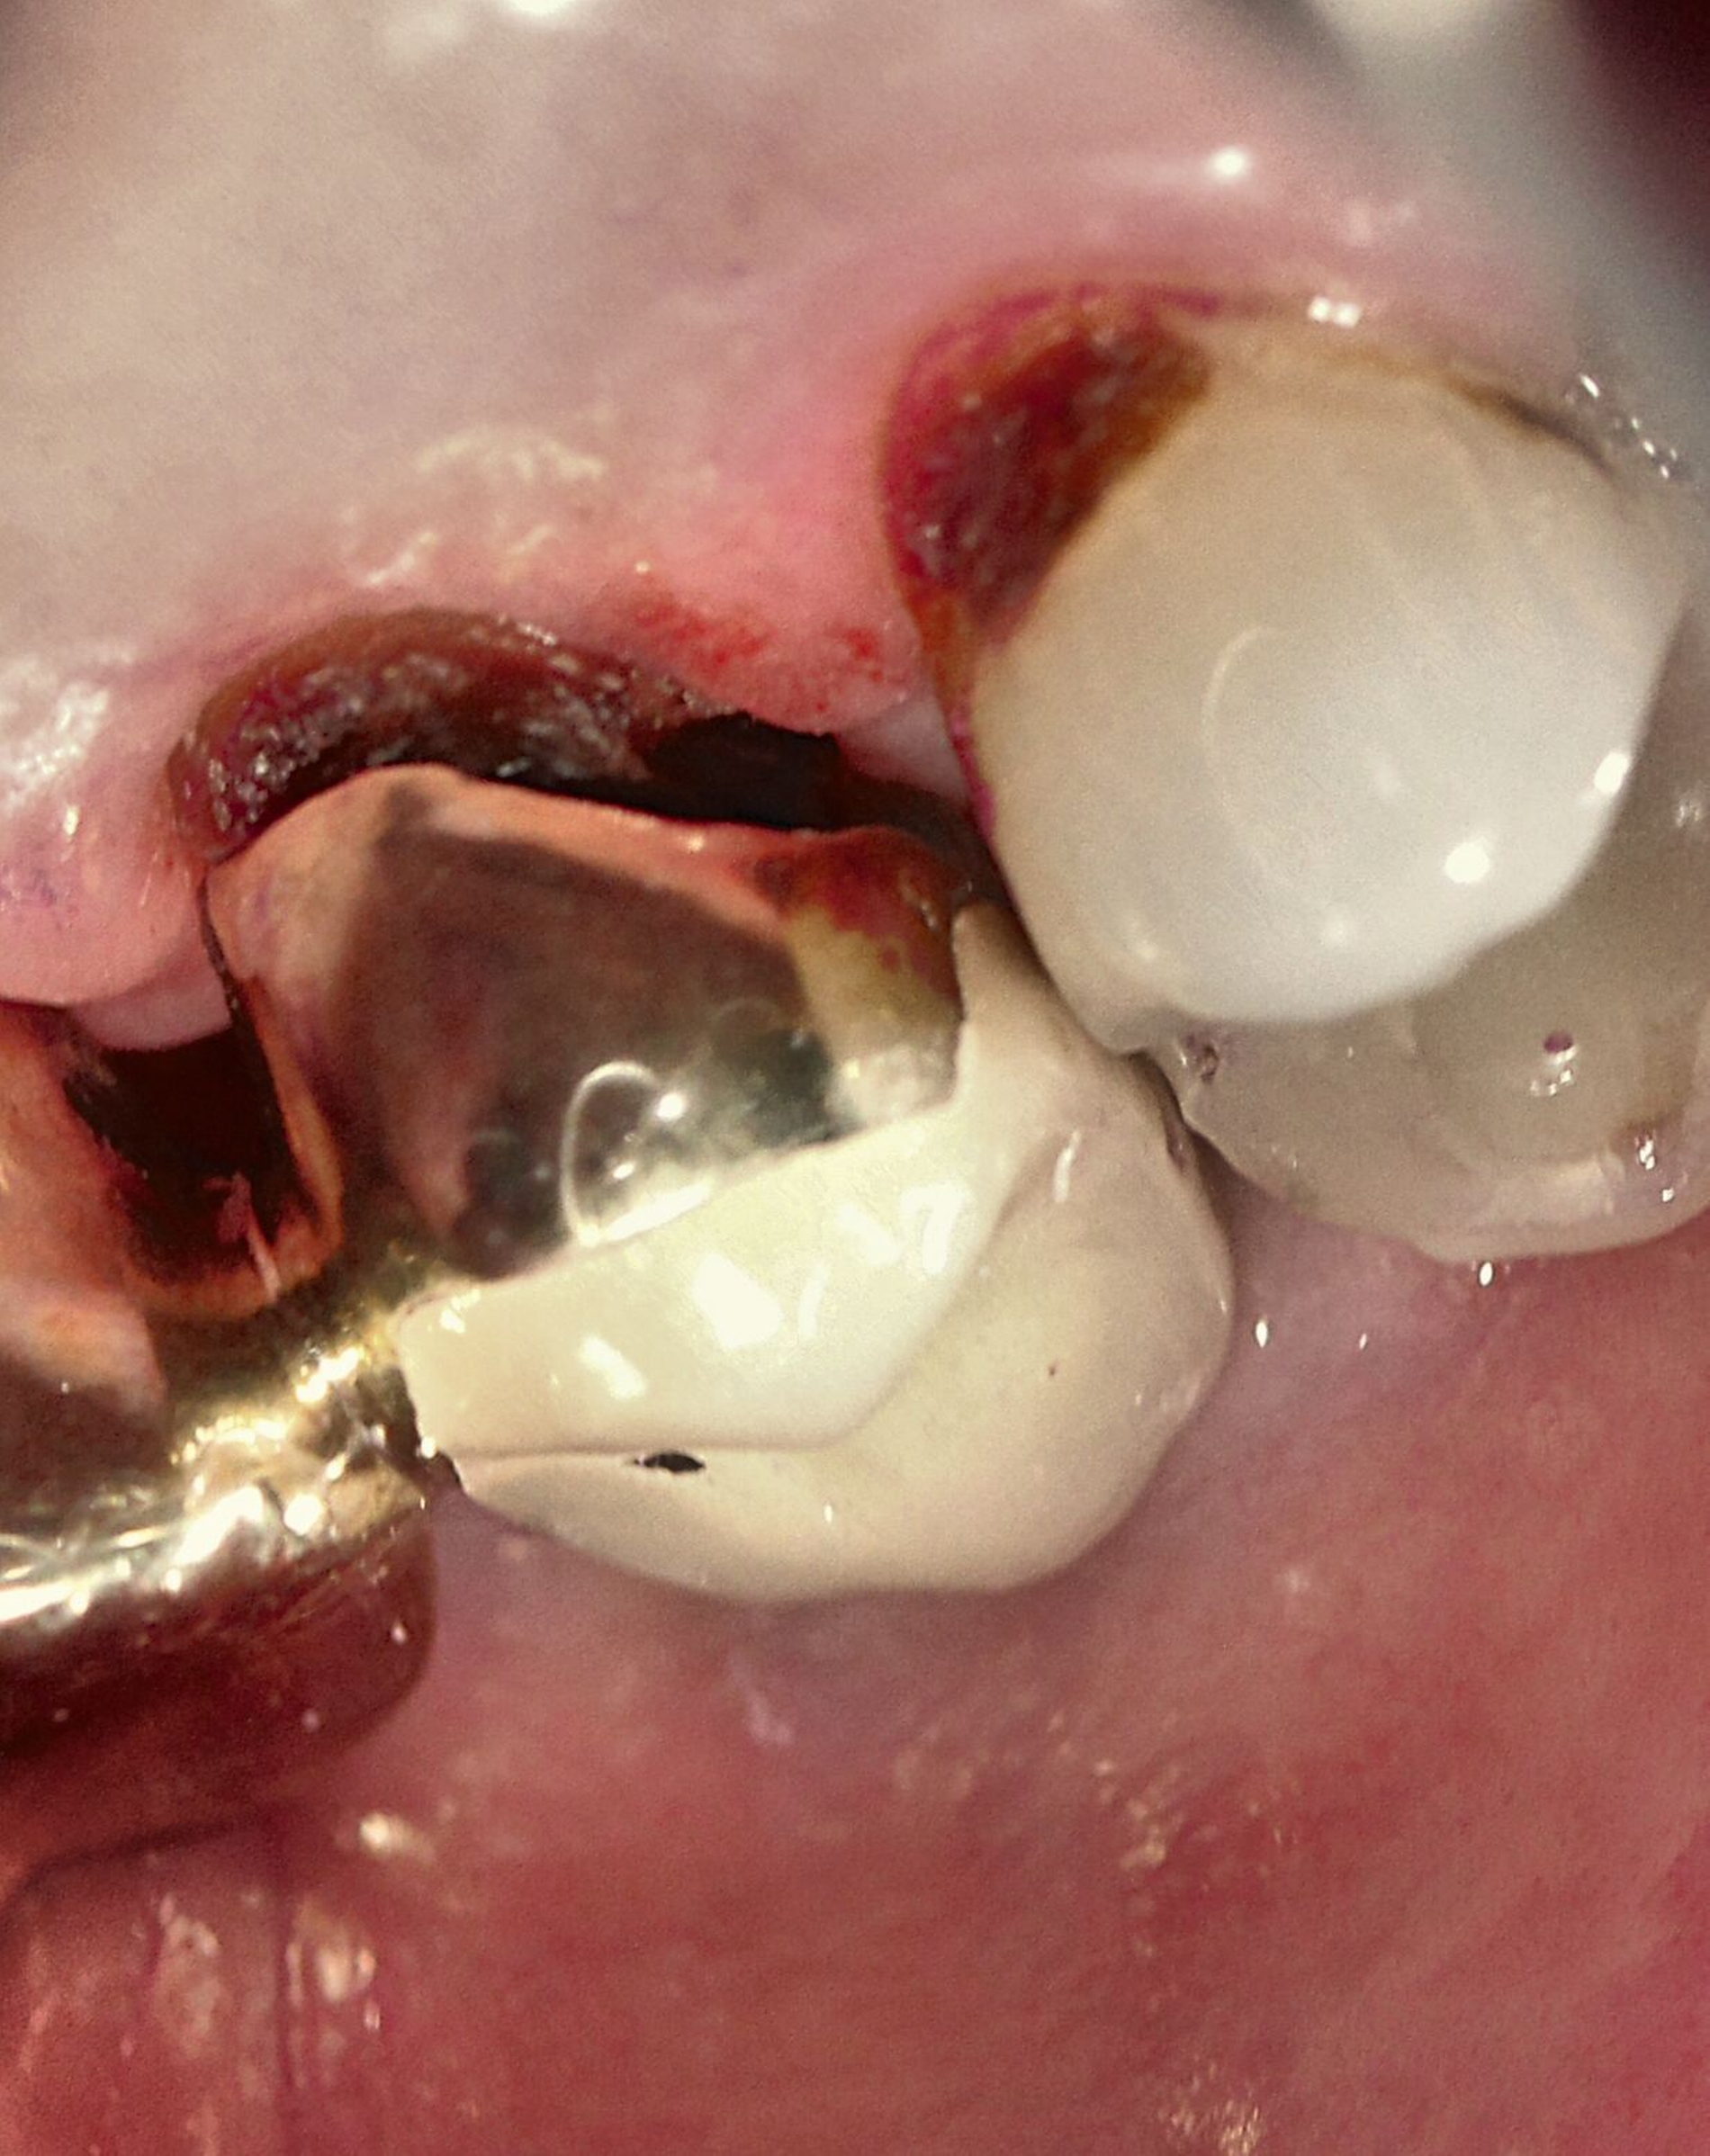

Silberdiamminfluorid ist eine wasserlösliche Verbindung, die aus Silberionen (Ag+), Ammoniak (NH₃) und Fluoridionen (F-) besteht. Ammoniak dient in dieser Verbindung als Stabilisator, indem es die Lösung alkalisch hält. Bei einer Konzentration von 38 Prozent entspricht das einer Konzentration von 44.800 ppm Fluorid und 255.000 ppm Silberionen. In seiner physikalischen Erscheinung ist SDF eine klare bis leicht gelbliche Flüssigkeit mit einem charakteristischen metallischen und leicht ammoniakartigen Geruch. Aufgrund der hohen Alkalität kann es bei Schleimhautkontakt zu leichten Reizungen kommen (Abbildung 2).

Eine bekannte Nebenwirkung bei Anwendung auf kariösen Läsionen ist die Schwarzfärbung des behandelten Bereichs (Abbildungen 3, 4). Verfärbungen können aber auch bei Applikation auf kariesfreien Wurzeloberflächen entstehen, diese sind jedoch mit einer professionellen Zahnreinigung gut zu entfernen (Abbildung 2).

Tatsächlich zeigt die klinische Erfahrung, dass es möglich ist, bei mehrmaliger Applikation innerhalb eines Vierteljahrs auch sehr aktive Läsionen mit taktil weicher Oberfläche trotz eingeschränkter Mundhygiene gut zu erhärten (Abbildung 4). Für die koronale Karies bei Kindern konnte die bessere Wirkung nach wiederholter Anwendung allerdings nicht bestätigt werden. [Smutkeeree et al., 2025].